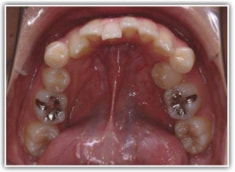

治療開始時

検査時パノラマレントゲン

特に小臼歯部に叢生があり、8番(親知らず)も埋伏しています。8番と7番の接触部分に吸収が若干あるような所見が認められます。